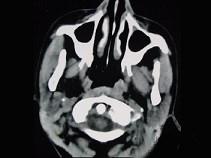

问题 16岁女性患者,右侧面颊部肿胀,CT扫描如图所示,应考虑为 ( )

选项 A、右侧咬肌区淋巴管瘤 B、右侧咬肌区慢性淋巴管炎 C、右侧咬肌区脂肪瘤 D、右侧咬肌区皮样囊肿 E、右侧咬肌区血管瘤

答案 E